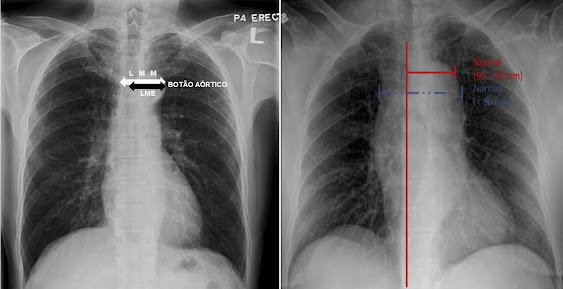

opacificado). Note-se abaixo a imagem comparativa do mesmo paciente em pé e

deitado (Fig. 1)[1].

Fig 1. Radiografia do tórax em PA ortostático (esquerda) e AP deitado (direita). Notar a diferença de qualidade das imagens, sendo que a imagem em PA permite melhor avaliação dos pulmões e estruturas mediastinais.

“Alargamento de mediastino” ou

“mediastino alargado” é definido como mediastino com largura mediastinal

máxima (LMM) > 6 cm em uma radiografia de tórax póstero-anterior (P-A)

vertical ou > 8 cm em radiografia de tórax ântero-posterior em decúbito

dorsal (A-P) medido a nível do botão aórtico[11] [12].

Fig. 9. Medição da Largura Mediastinal

Máxima (LMM)

e Largura Máxima Mediastinal Esquerda

(LME)